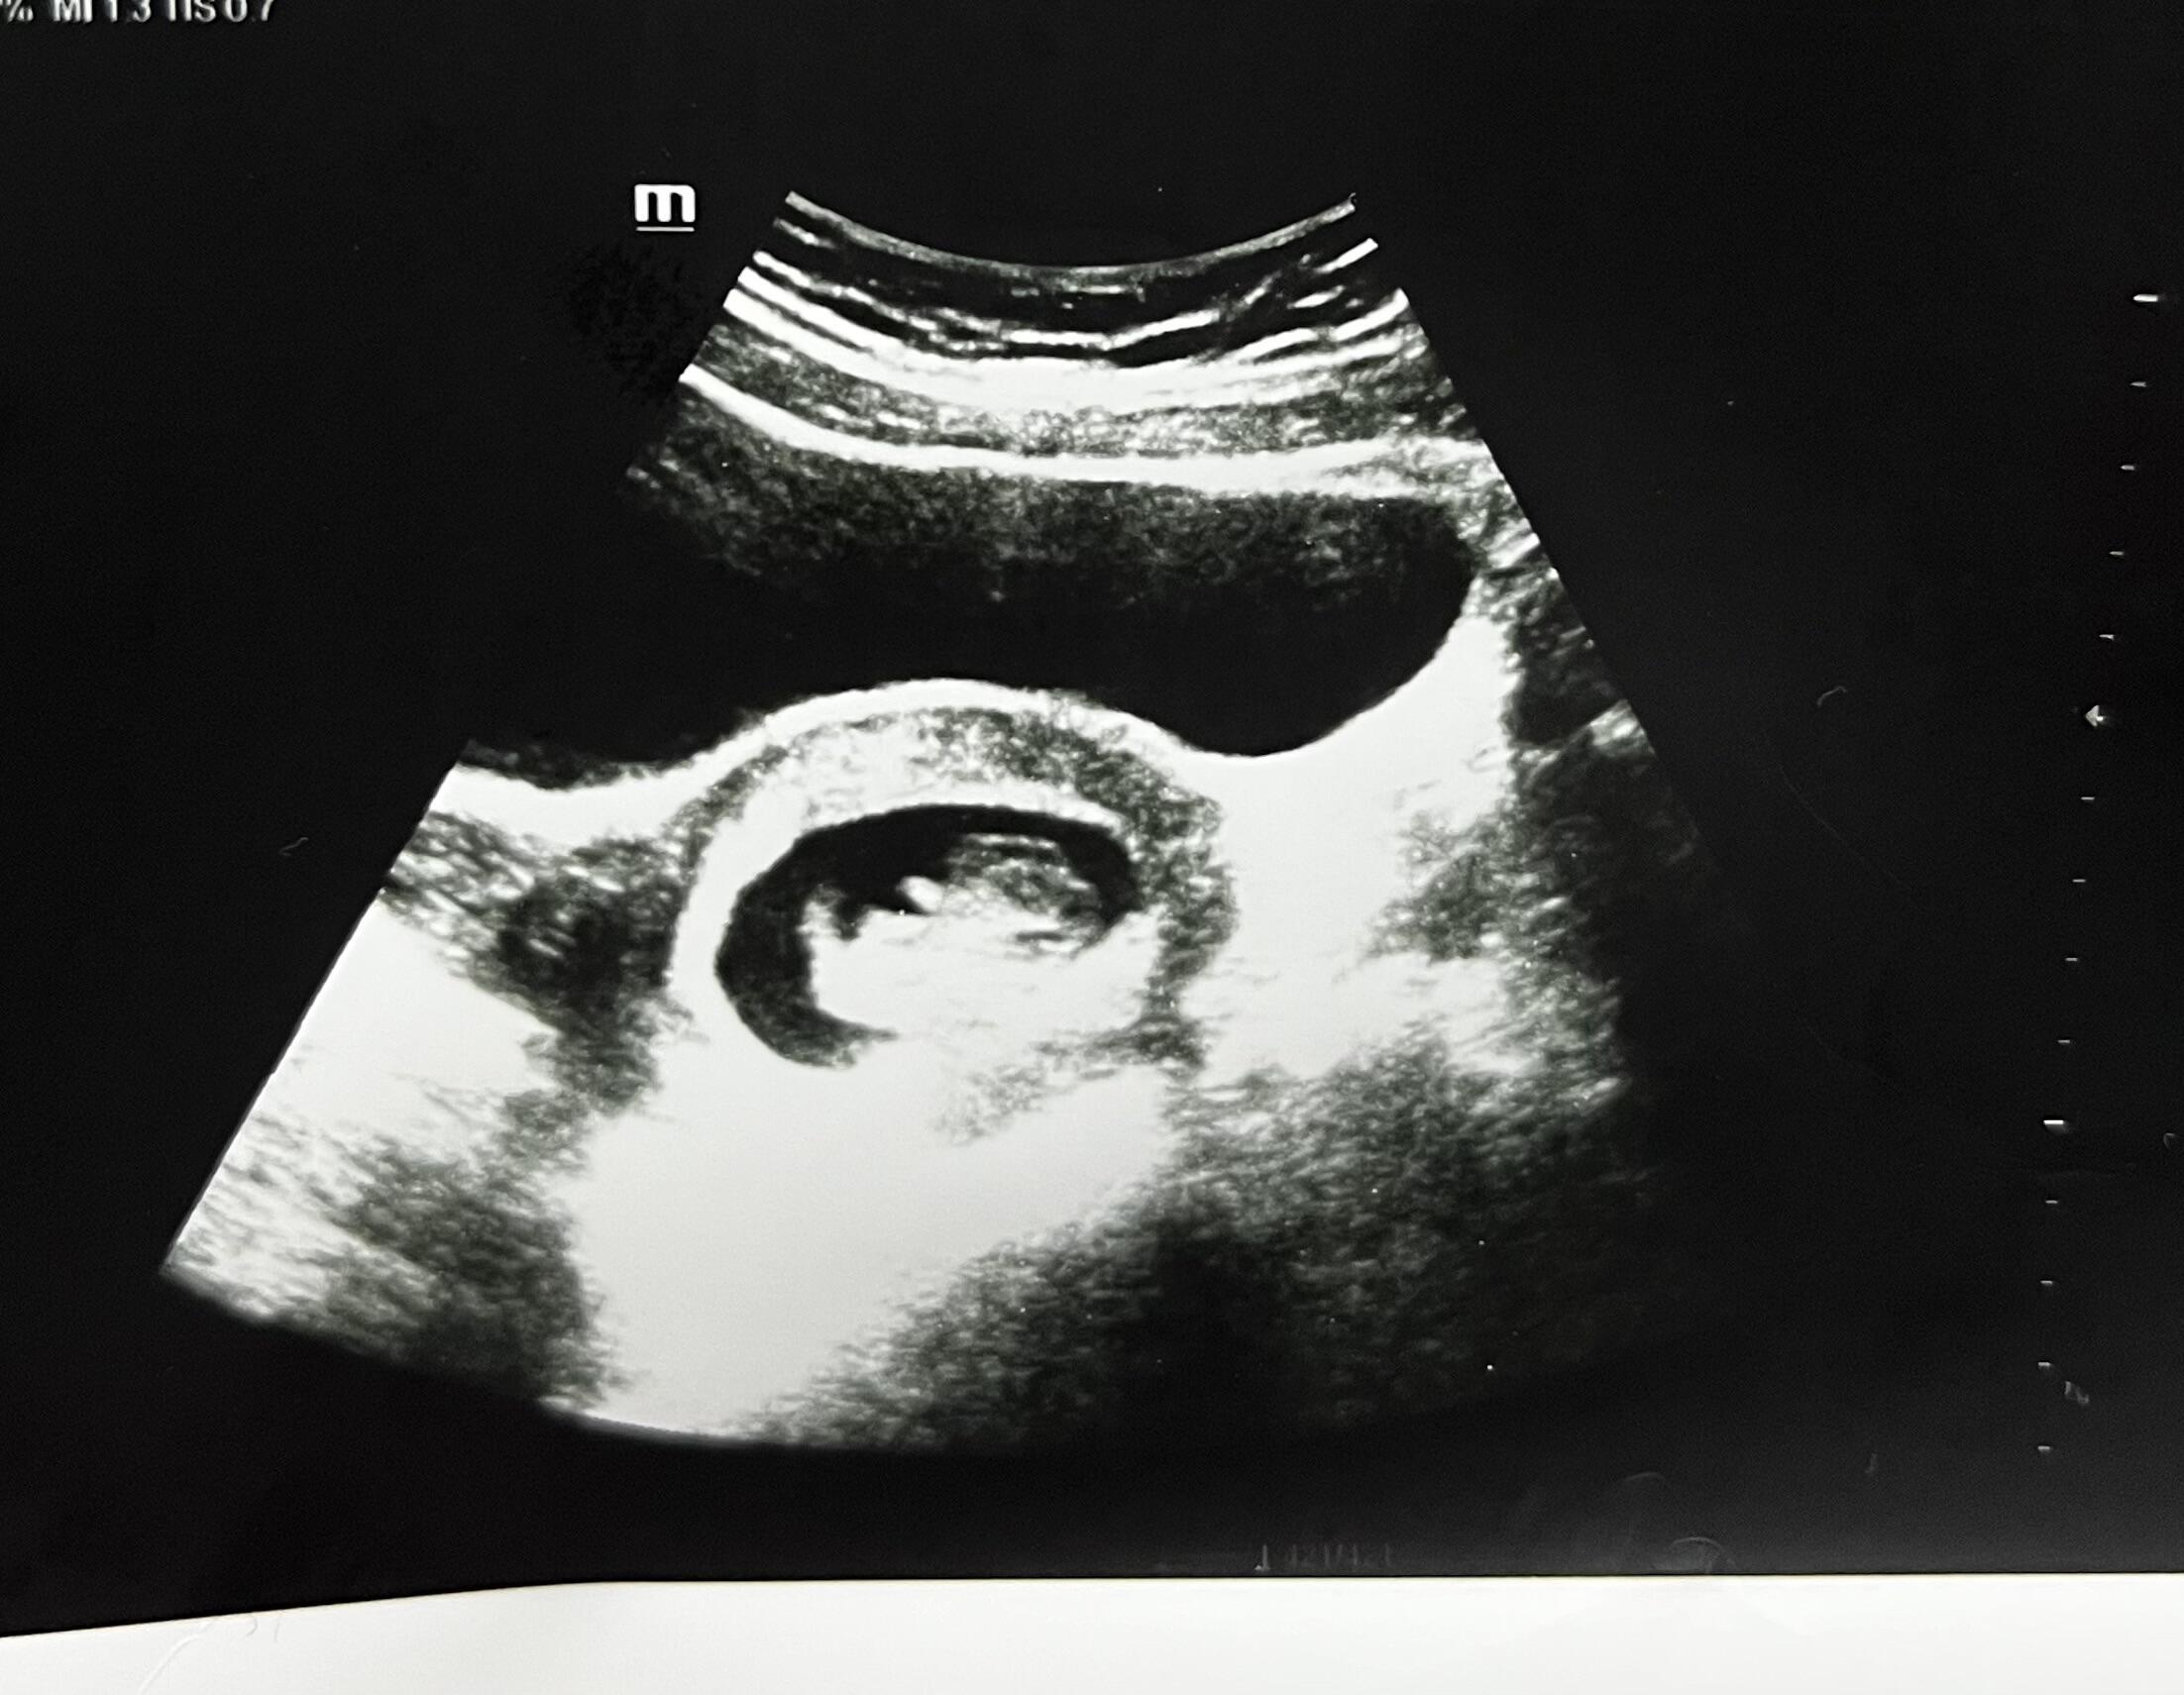

Ben hiç anlamıyorum canım ama nub teorisine göre bir kaç video izledim farklı açidan gözüken var mı

Canım video olarak var resim hiç yok bunuda o şekilde aldım bende hiç anlamıyorum